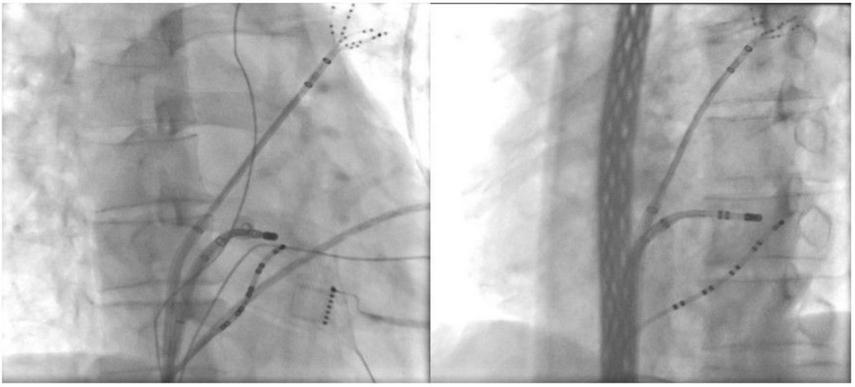

FIGURE 2

Ablation target of the CSD-LA electrical connection under fluoroscopic. *(Left) right anterior oblique view; *(Right) left anterior oblique view.